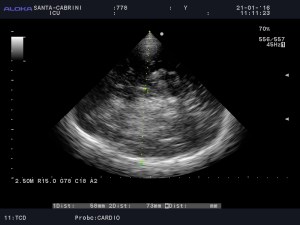

However, there is a clear asymmetry in the hemispheres (not due to gain difference), with the distal hemisphere (RT) showing increased echogenicity:

Also, there is a midline shift:

This suggested an acute and severe process in the right hemisphere. A few hours later, the CT scan showed the following: